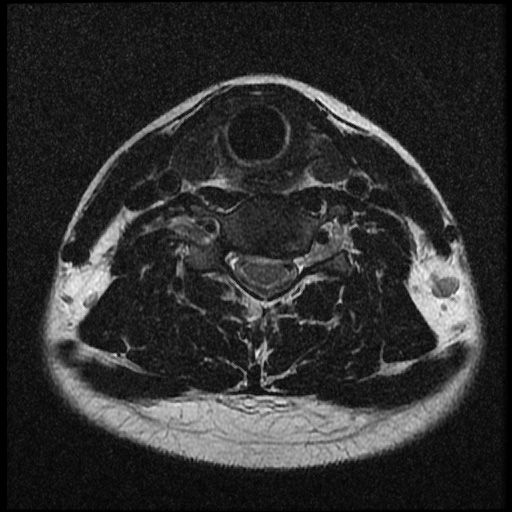

이 MRI 사진은 21년도 사고 당시 찍은 MRI 사진 입니다. 확인 부탁드립니다~

전체 mri를 다 봐여겠지만 보여주신 mri 컷에서는 의미있는 경추 디스크탈출이 보이지 않습니다.